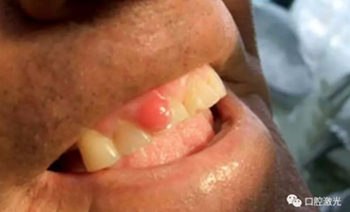

術(shù)后1周、4周、6個月以及1年對患者進行追蹤觀察。1周復(fù)診時,重點了解疼痛、出血以及水腫的情況。其結(jié)果為沒有出現(xiàn)上述情況。所有的患者都可以術(shù)后立即恢復(fù)正常的生活、學(xué)習(xí)、工作活動。并且,術(shù)后沒有使用止疼藥和消炎藥。在4周時,評估傷口的愈合情況,所有的患者都恢復(fù)很好,沒有出現(xiàn)并發(fā)癥現(xiàn)象。在6個月至1年期間,沒有出現(xiàn)任何形式的復(fù)發(fā)。因此,患者對激光手術(shù)的效果評價十分高。

通過口腔激光對齦瘤進行手術(shù)切除有著眾多優(yōu)勢。其中,由于對血紅蛋白的吸收率很高,半導(dǎo)體激光有著優(yōu)秀的凝血效果。不但術(shù)中出血量大大減少,同時給醫(yī)生提供了一個良好的手術(shù)視野。術(shù)后的優(yōu)勢也是顯而易見的,傷口愈合的速度更快,沒有疼痛和水腫的發(fā)生。大大縮短的手術(shù)時間,減少了患者對手術(shù)治療的恐懼心理。因此對于患者和醫(yī)生來說都十分受益于口腔激光。